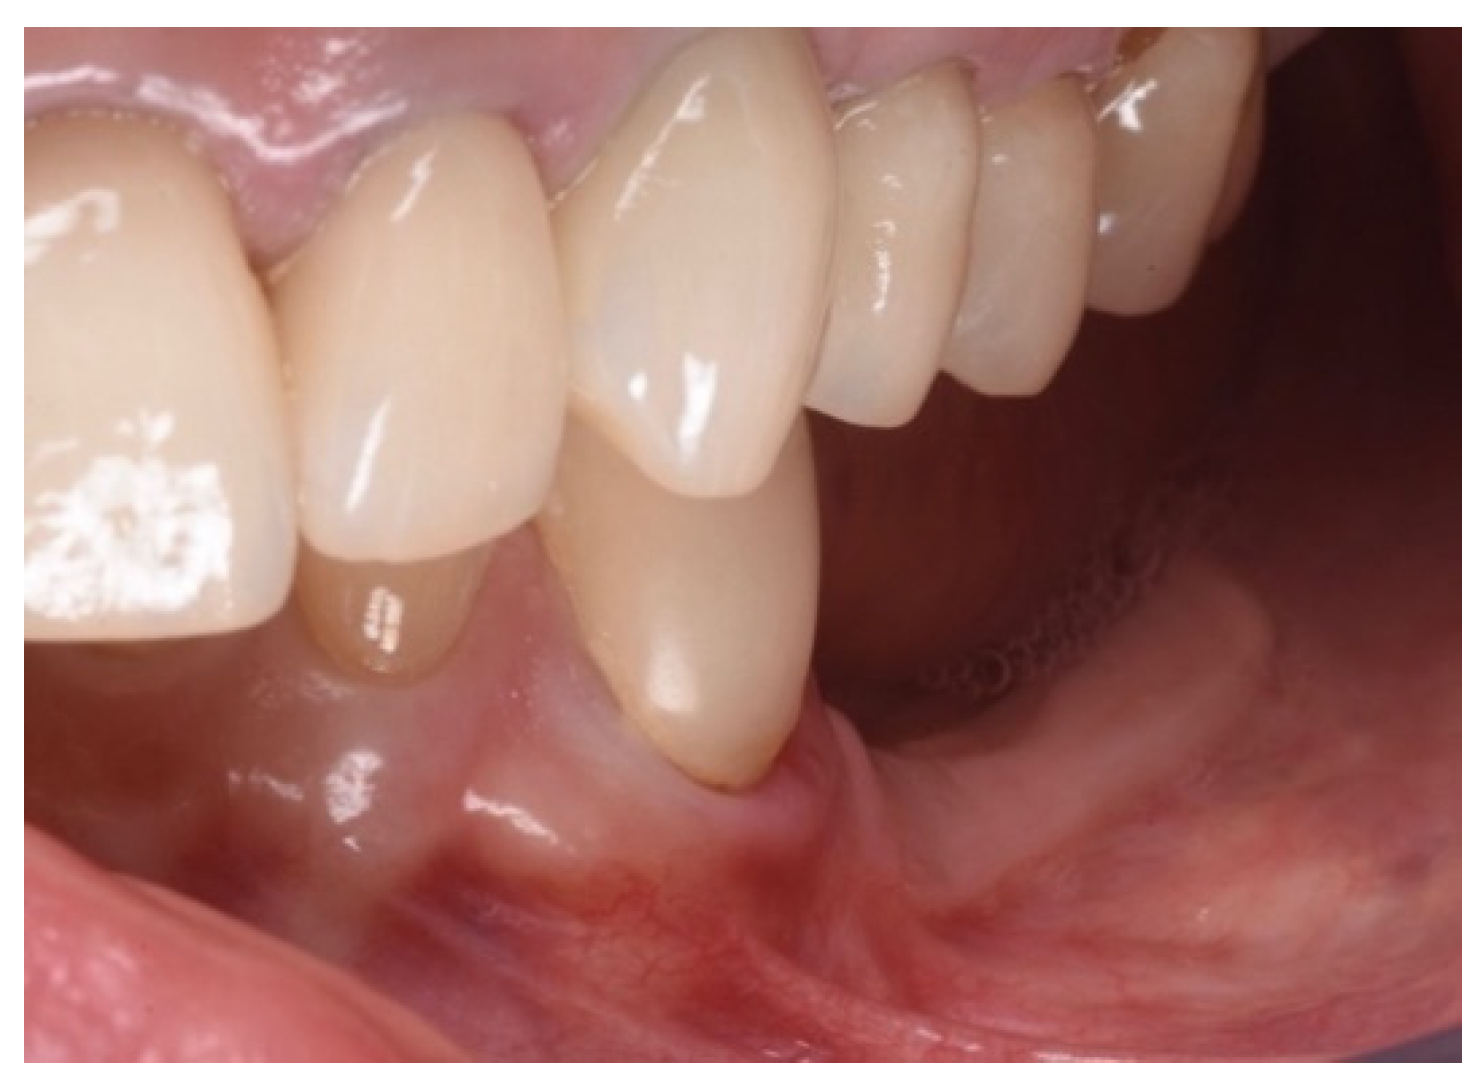

3.2. Soft Tissue Augmentation

| T1 | Mucogingival Surgery (0 months) | Free gingival graft |

| T2 | Guided Bone Regeneration (3 months) | GBR with Flex Cortical Sheet (Bioteck SpA, Arcugnano, Italy) |